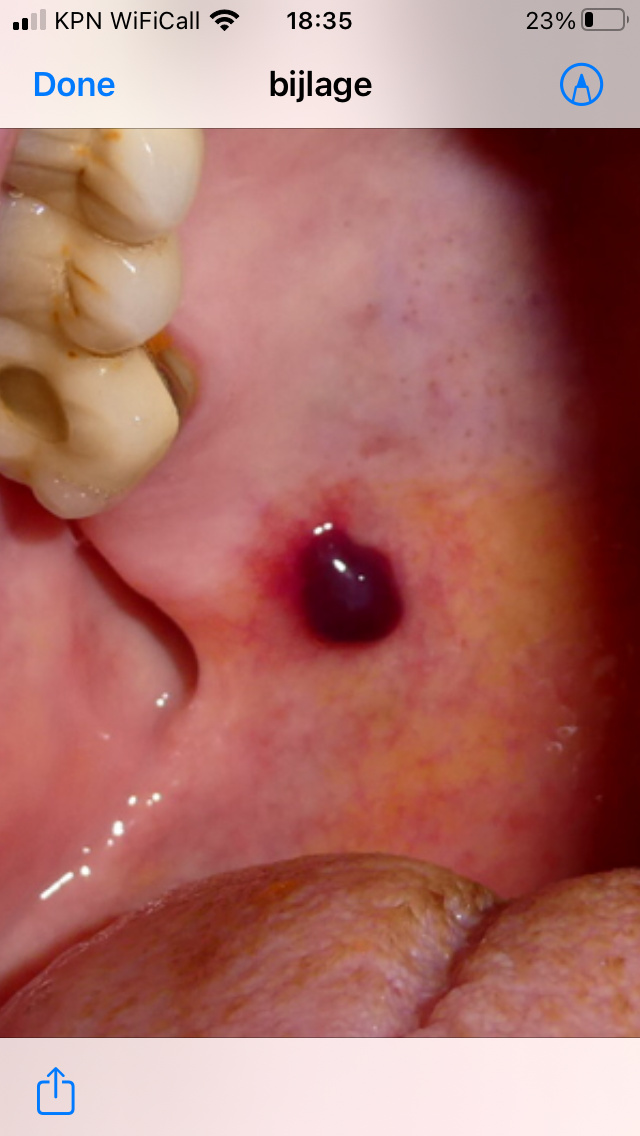

Beste, ik heb de afgelopen maanden een aantal maal bloedblaar op mijn gehemelte gehad na druk door voedsel in mijn mond. Dit was ook koud voedsel. Het is dus niet door hitte maar alleen door druk veroorzaakt. Het waren soms grote blaren, soms een 2 euromunt groot en het genezen duurde lang en ik vond het flink pijnlijk. Tot hoofdpijn en pijn in de halsspieren aan toe.  In de literatuur hierover kom ik tegen dat er een link gelegd wordt met inhalatie corticostoiden. Zijn er artsen of meer mensen die ook puffen die hier bekend mee zijn? En is er iets te doen om het te voorkomen behalve oppassen dat je niets hards tegen je gehemelte aandrukt?

Ik heb vrij regelmatig bloedblaren in mijn mond, vaak na het eten van harde broodjes of chips, met name Pringles zijn berucht. Het is voor mij hieuw dat het door de inhalatie corticosteroïden kan komen.